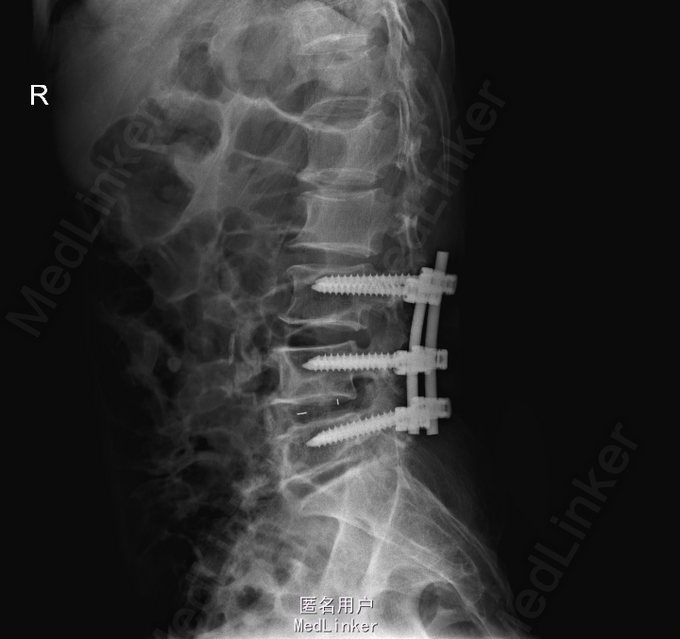

查体:左侧小腿外侧、足背感觉减退,右侧正常,双侧屈髋、伸膝、踝背伸肌肌力5级,左侧踇背伸、跖屈肌肌力4级,右侧踇背伸、跖屈肌肌力4-5级,双侧巴氏征阴性,直腿抬高试验左侧30°阳性,右侧阴性。 辅助检查: X-ray:腰椎退行性变,腰椎节段性性不稳 MR:腰椎间盘突出,腰3/4,4/5,腰4/5节段明显

诊断:腰椎椎管狭窄 处理: 1、完善相关辅助检查,明确诊断,有无手术指证; 2、完善手术评估,有无手术禁忌,手术风险及并发症; 3、在全麻下行腰椎后路减压,腰3/4左侧椎板减压,腰4/5椎间Cage植骨融合内固定术

随访 术后患者下肢麻木感觉较前好转,左侧踝背伸、跖屈肌力4级+,左侧肢体抬高试验阴性。术后MR检查减压彻底 讨论:1、腰椎椎管狭窄手术指证的把握,腰椎后路手术,腰椎椎间融合与椎板减压的选择? 2、术中探查如无明显间盘突出,以椎管骨性狭窄为主,可行腰椎后路椎板减压为主。